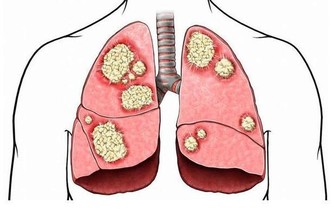

冬季防止寒邪和風邪入侵身體,尤其是做好頭部腳部以及胸腹部的保暖。當寒氣入侵胸腹部時會損傷到陽氣,從而誘發心髒病及胃腸道疾病。天氣寒冷時會讓頭部血管突然收縮,引起頭痛頭暈,增加了患上腦血管疾病的機率,甚至會誘發意外。腳離心臟最遠而且血液供應慢,再加上皮下脂肪層薄,保暖性比較差,當受寒時會引起呼吸道黏膜毛細血管突然的收縮,下降了抵抗力,增加了患上上呼吸道感染的風險。